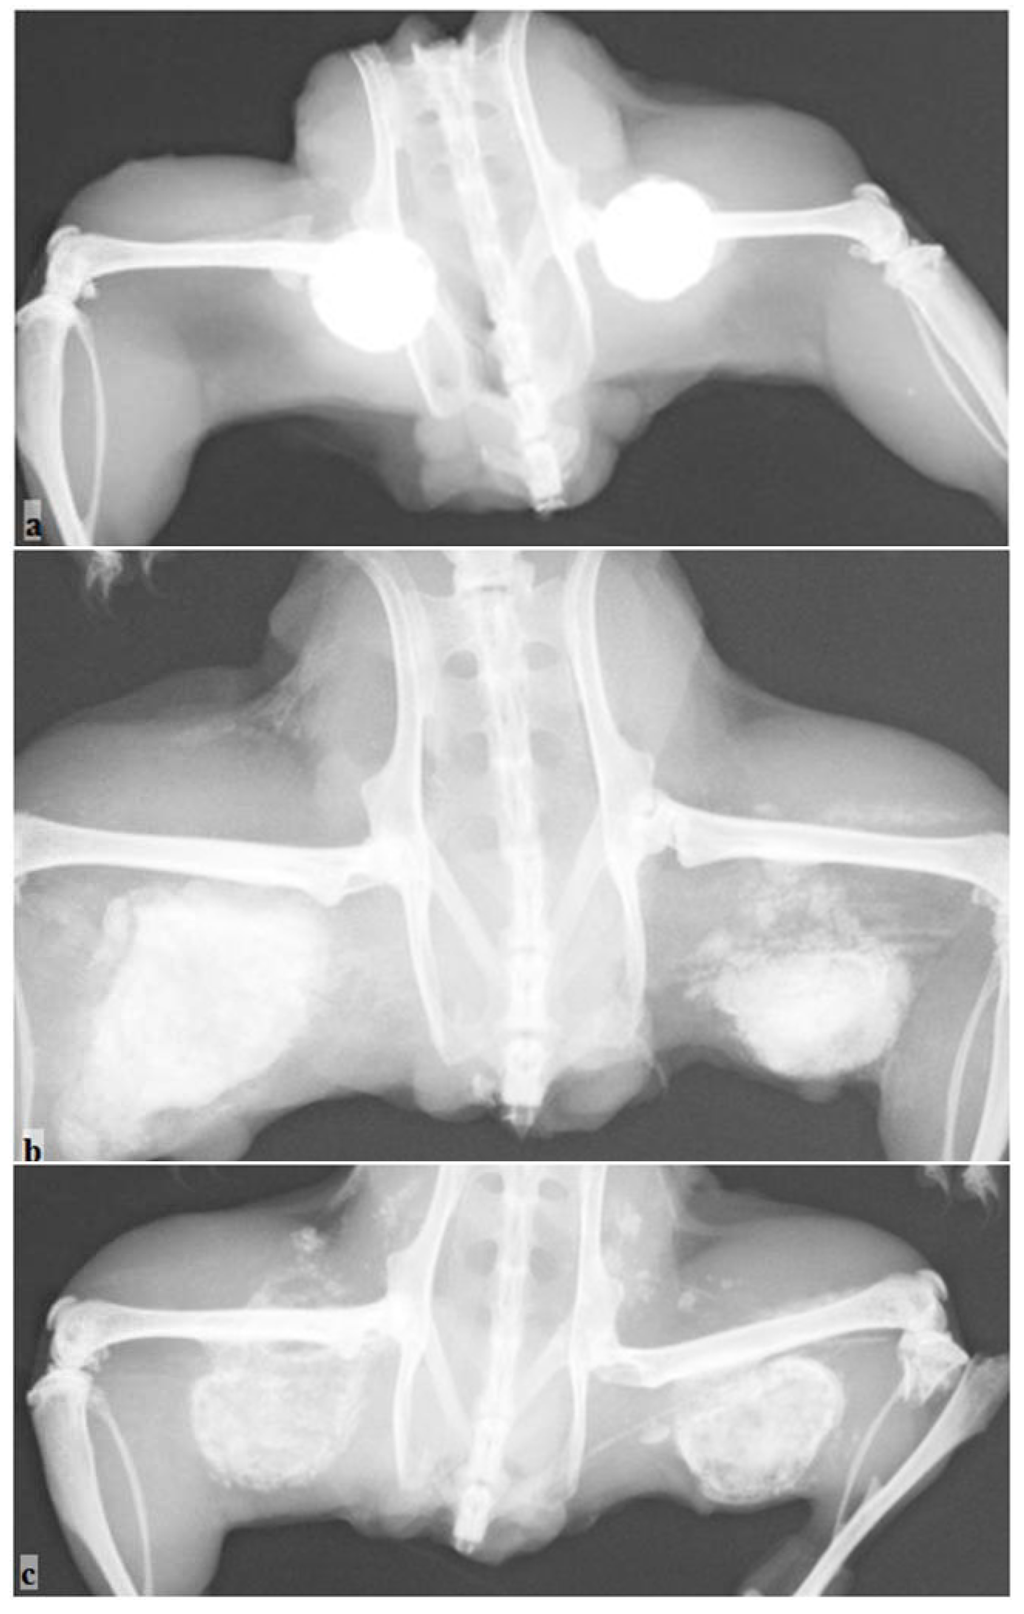

For group a, the radiographic evaluation of the hydroxyapatite-tricalcium phosphate-calcium sulfate discs (HAP:TCP:CS 30:60:10) demonstrated some bone formation outside the active implant; however, the control implants remained intact (Table 1, Figure 3a). The measurement area was significantly higher for the active implants compared to the controls (p < 0.01). The harvesting analysis indicated that this new formation was bone-like. The histological evaluation demonstrated that endochondral bone formation occurred in the active sample and not in the control sample (Figure 4a, b).

For group d (calcium sulfate hemihydrate discs), the radiography analysis revealed some new bone formation, and significant differences (p < 0.01) were apparent between the active and control groups (the control group had visibly resorbed) (Table 1, Figure 3b). However, the harvesting and histological analysis showed that no new bone was found in the samples (Figure 4c, d).

Figure 3. Radiographic evaluation of the new bone formation in the mouse pouch model using different carriers with the reindeer bone protein extract. The control without the bone protein extract is located on the right side, and the active implant on the left side: (a) HAP/TCP/CS 30:60:10; (b) CS hemihydrate; and (c) CS dihydrate + stearic acid.

For group f (calcium sulfate dihydrate—stearic acid), the radiographic analysis and harvesting analysis revealed new bone formation in the active implant group (Table 1, Figure 3c). The difference between the active implants and the controls was statistically significant (p < 0.01). Also, histological analysis revealed clear bone formation and mature and calcified cartilage in the active sample (Figure 4e). No visual bone formation was apparent in the control sample (Figure 4f).